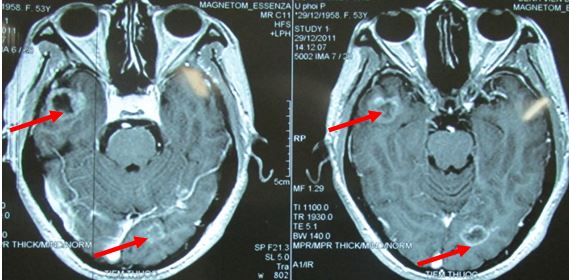

- Chụp MRI sọ não

Hình 2: hình ảnh MRI sọ não cho thấy di căn não đa ổ

Hình 8: U di căn não đa ổ trước điều trị

Hình 9: tổn thương não tiêu biến hoàn toàn, lâm sàng hoàn toàn bình thường